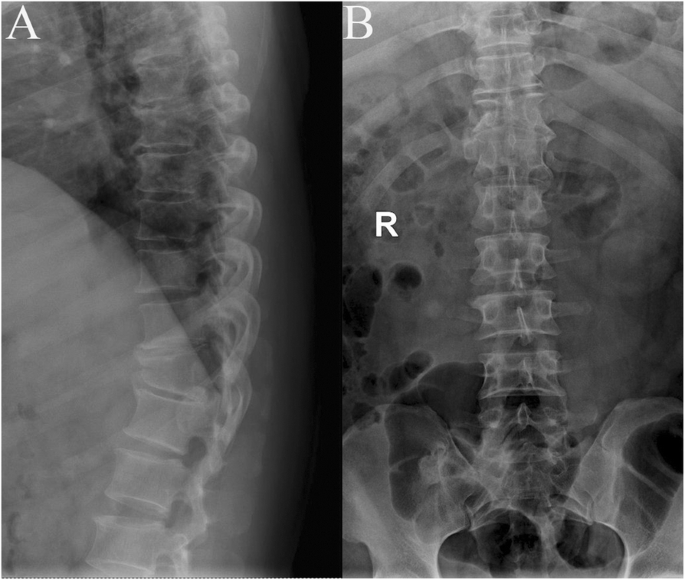

Radiography Showed T11 Vertebral Plana And Irregular T10 With Slight Download Scientific Diagram